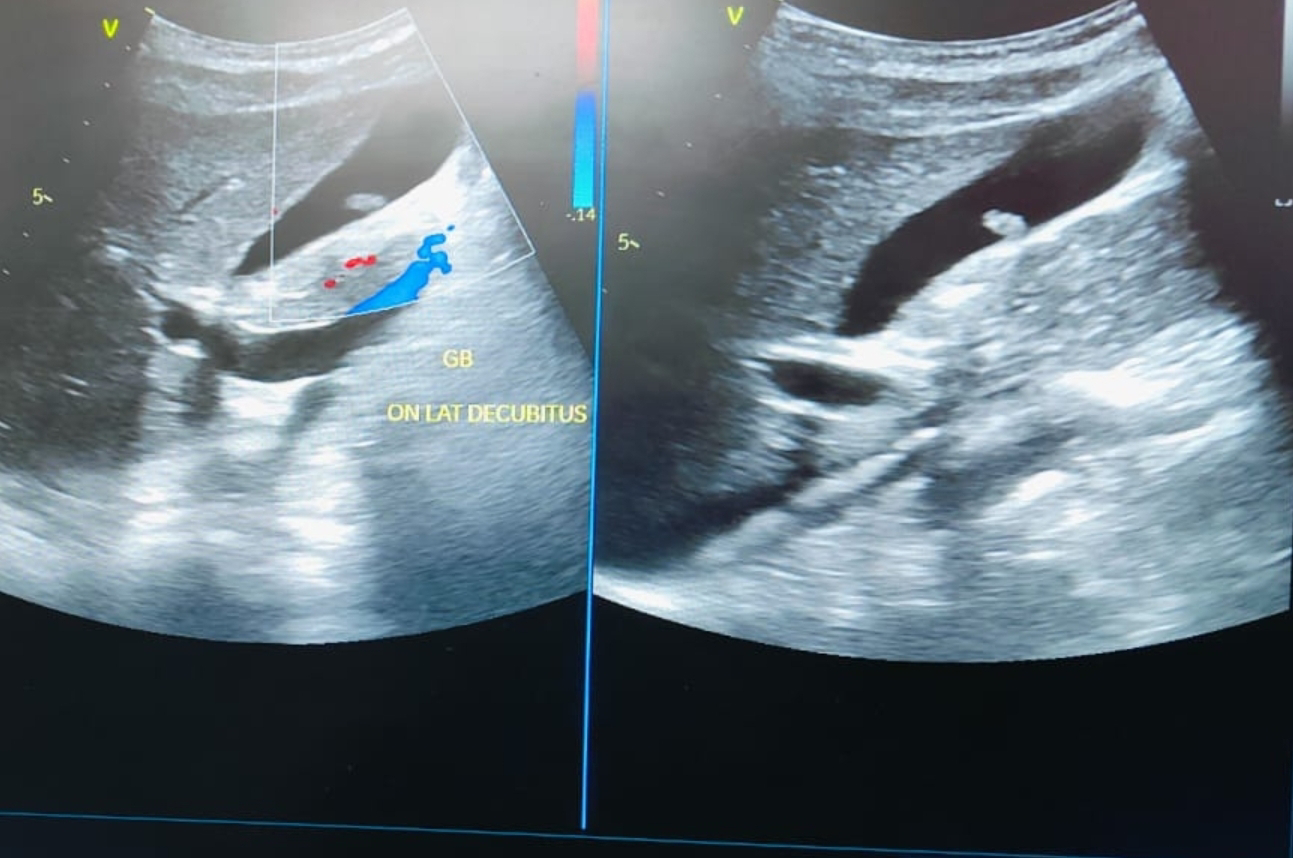

# Ultrasound and Color Doppler Imaging of Gallbladder Polyp:

- Ultrasound is the initial imaging modality for gallbladder polyps due to its affordability, accessibility, and safety.

- Color Doppler imaging can assess blood flow within the polyp, aiding in differentiation between benign and malignant lesions.

**GB Polyp without Vascularity:

- Lack of vascularity on color Doppler suggests a higher likelihood of a benign polyp, often a cholesterol polyp.

- However, absence of flow doesn't guarantee benignancy. Further evaluation may be needed.

Ultrasound images of the polyp on inferior wall of GB:

Color Doppler image: no vascularity